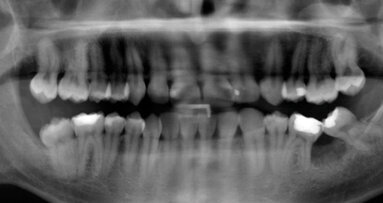

La pulpectomia è un trattamento che prevede la rimozione dell’intero organo pulpare, sia coronale che radicolare. È indicata nei casi in cui la polpa è vitale ma irreversibilmente infiammata o non vitale a causa di lesioni cariose avanzate o di traumi. Il fine del trattamento endodontico è quello di controllare l’infezione e quindi eliminare i batteri patogeni del sistema canalare.

Tale trattamento è influenzato da vari fattori legati principalmente all’anatomia radicolare, alla sottigliezza del pavimento della camera pulpare, all’impossibilità di stabilire l’esatta collocazione del forame apicale, sia clinicamente che radiograficamente, effetto dovuto al rimaneggiamento che avviene durante il processo di rizalisi. A oggi la misurazione elettronica della lunghezza di lavoro appare il metodo più affidabile per evitare una sovra strumentazione.

La metodica prevede il trattamento del sistema canalare finalizzato a promuovere una buona penetrazione degli irriganti mediante una alesatura con strumenti a bassa conicità al fine di non creare un eccesivo indebolimento delle già sottili pareti radicolari, dovuto al processo di rizalisi in atto. I materiali utilizzati per la chiusura devono essere esclusivamente riassorbibili ma in grado di garantire un adeguato sigillo del terzo medio-coronale del canale radicolare onde evitare possibili contaminazioni batteriche del sistema endodontico.